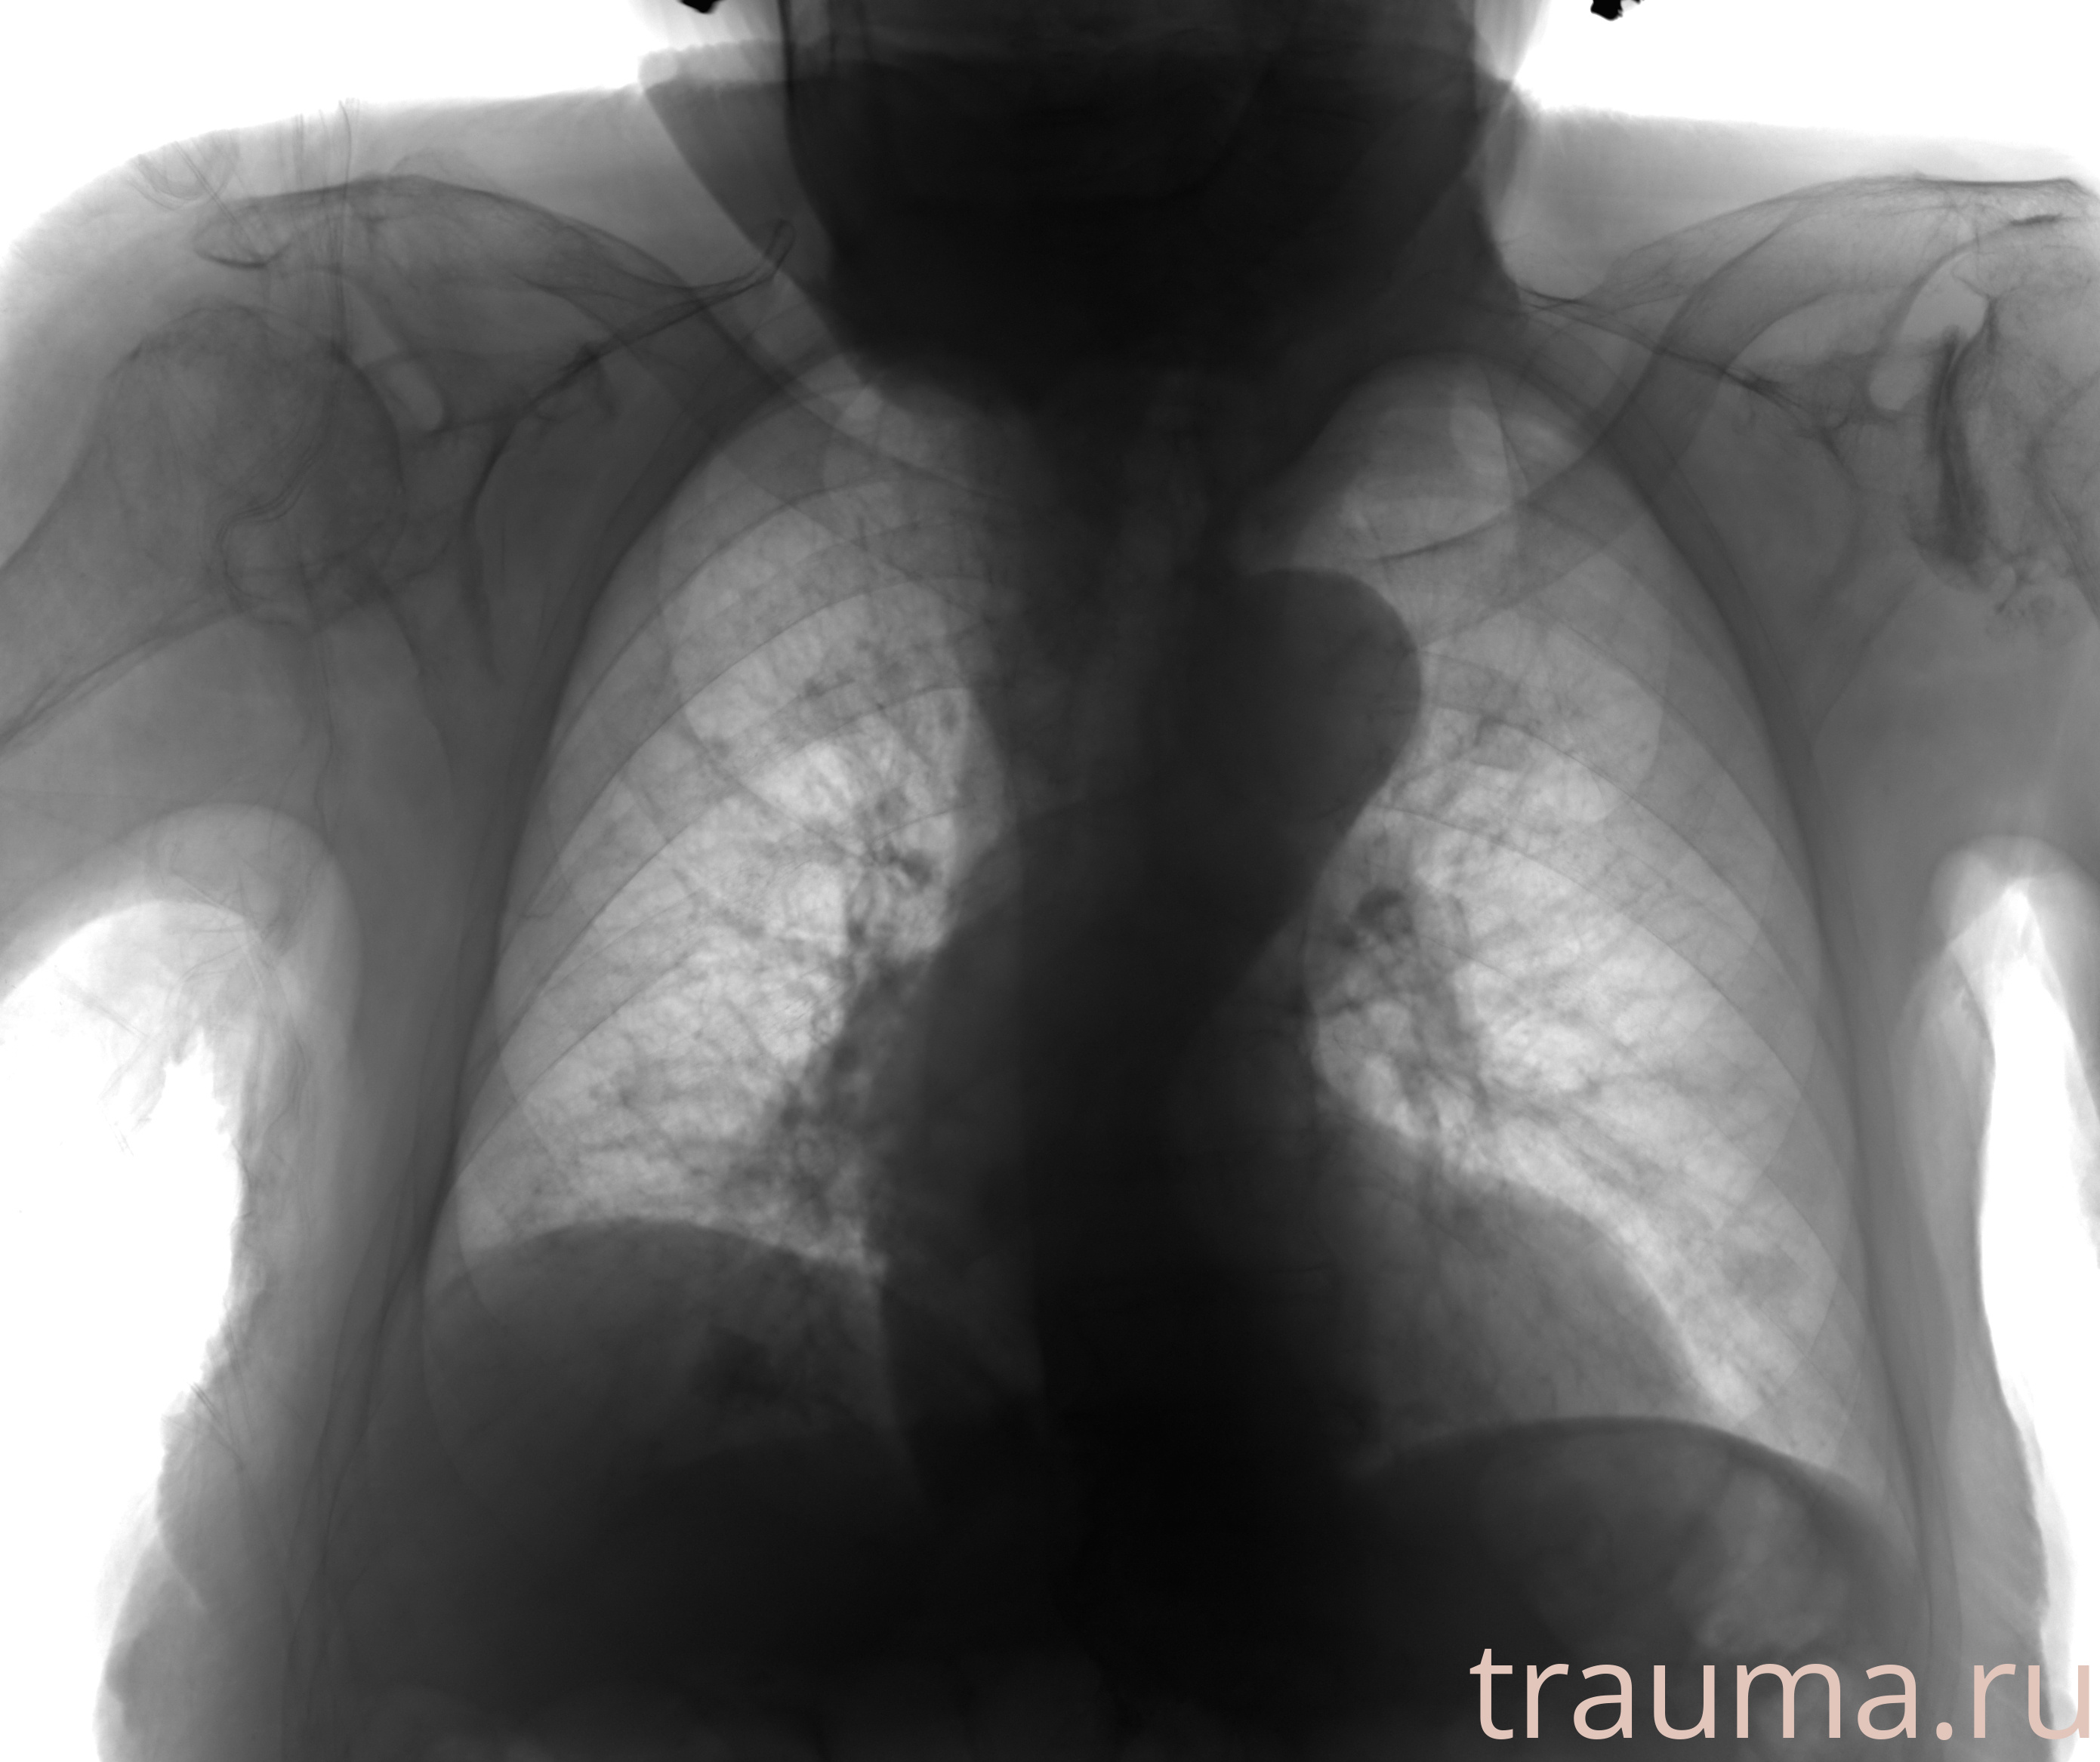

Рентгенограммы

Рентген на дому: по вашему адресу приезжает врач-рентгенолог, травматолог-ортопед с мобильным рентгеновским аппаратом, проводит диагностику травмы или заболевания, делает необходимые рентгенограммы, дает рекомендации по дальнейшему лечению. Получить качественные снимки в домашних условиях возможно благодаря уникальной методике, разработанной МосРентген Центром для института  Склифосовского

Яркость: 1   Контраст: 1   Инвертировать: 0 Увеличение: 1